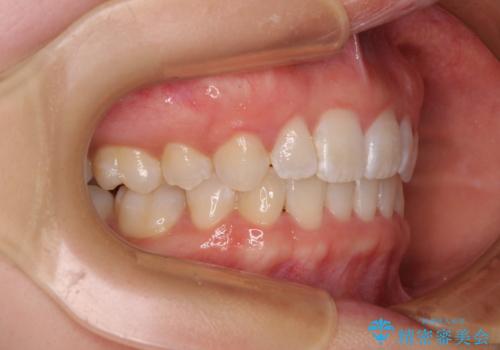

- 上下前歯のデコボコを気にして来院された患者様です。

口元の突出感はあまりなかったものの、デコボコを非抜歯で改善すると出っ歯になる可能性があるため、上下左右の第一小臼歯4本を抜歯し、ワイヤー装置にて矯正治療を行うこととしました。

口元の突出感がない分、奥歯を前方に移動させる必要がありましたが、予定の2年間で無事に治療を終えることができました。